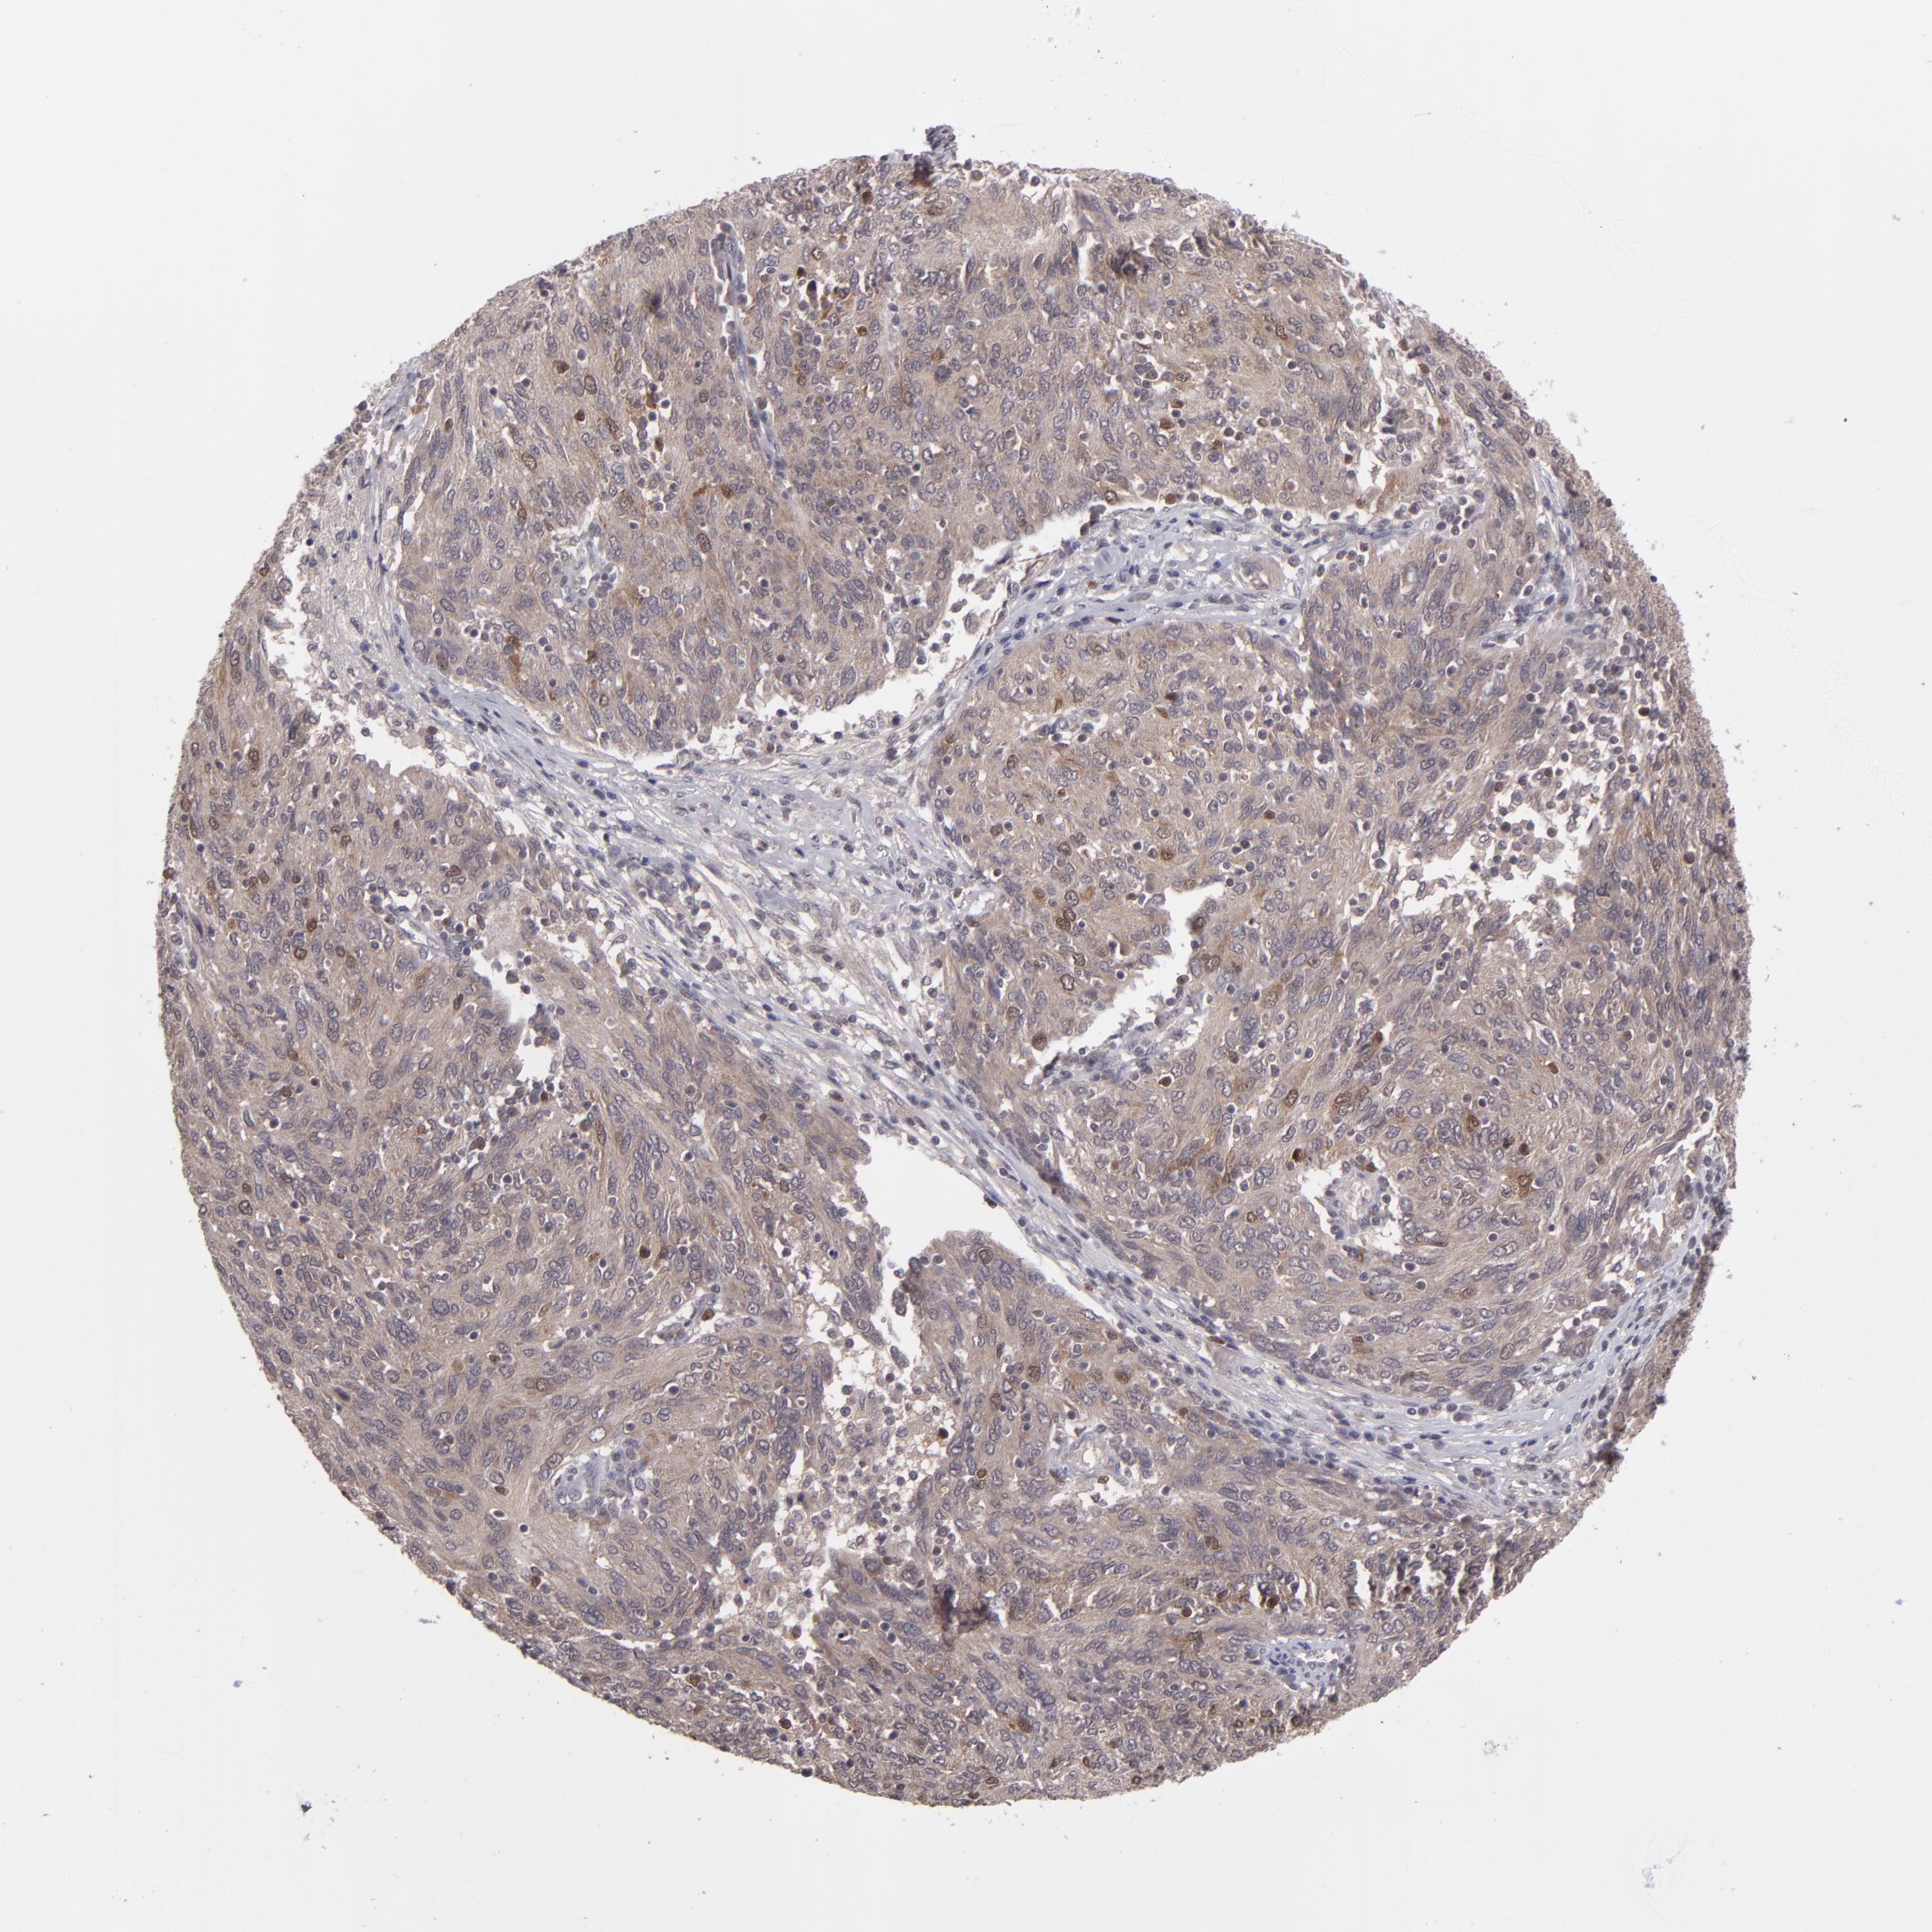

OVARIAN CANCER - Protein expressioni

A mouse-over function shows sample information and annotation data. Click on an image to view it in a full screen mode. Samples can be filtered based on level of antibody staining by selecting one or several of the following categories: high, medium, low and not detected. The assay and annotation is described here.

Note that samples used for immunohistochemistry by the Human Protein Atlas do not correspond to samples in the TCGA dataset.

Antibody stainingi

Antibody staining in the annotated cell types in the current human tissue is reported as not detected, low, medium, or high, based on conventional immunohistochemistry profiling in selected tissues. This score is based on the combination of the staining intensity and fraction of stained cells.

Each image is clickable and will lead to virtual microscopy that enables deeper exploration of all samples and also displays staining intensity scores, fraction scores and subcellular localization as well as patient and tissue information for each sample.

Antibody HPA074922

Antibody CAB002784

Cystadenocarcinoma, serous, NOS